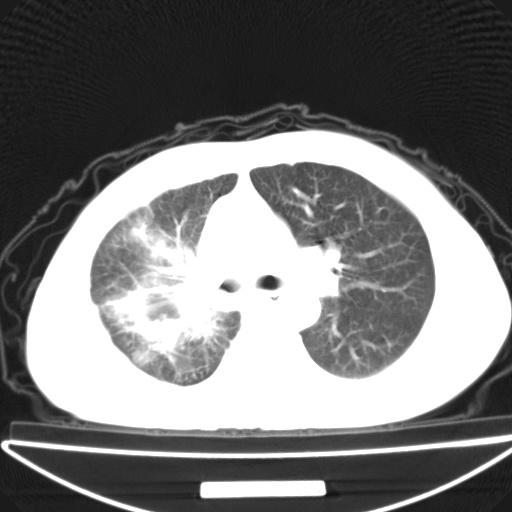

以下是引用jsgdoctor在2008-11-6 22:12:00的发言:[br]右主支气管壁明显增厚,管腔狭窄.考虑为右侧中央型肺癌伴阻塞性炎症\\肺脓肿.

以下是引用zjzjr在2008-11-6 20:25:00的发言:[br]中心型肺ca,合并阻塞性肺炎

以下是引用zsl6918在2008-11-6 19:43:00的发言:[br]右侧中心性肺癌(鳞癌)